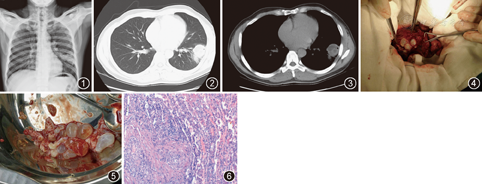

患者男,44岁,汉族,主因"咳嗽、咳痰1个月,加重1 d"于2014年12月28日入院。1个月前患者受凉后出现咳嗽、咳痰,痰呈黄色脓痰,伴痰中带血,无发热、寒战、乏力、胸痛及呼吸困难等症状,自服罗红霉素(具体剂量不详),咳嗽稍减轻,黄色脓痰变为白色黏痰,10 d就诊于当地医院,给予"阿奇霉素、喜炎平注射液"静脉滴注,患者感咳嗽、咳痰等症状无明显缓解,1 d前患者自觉上述症状加重,我院门诊行X线胸片检测示左肺下叶高密度渗出影(图1)。遂以"肺部阴影"收住我科,起病以来精神可,饮食睡眠欠佳,大小便正常,体重无明显变化。患者既往体健,有吸烟史20年,既往体健,否认肺结核病史,家住农牧团场,有狗类接触史。体格检查:体温36.7 ℃,脉搏80次/min,呼吸20次/min,血压120/70 mmHg(1 mmHg=0.133 kPa)。浅表淋巴结未触及肿大,耳鼻无异常,颈软,无抵抗,甲状腺不大。双肺呼吸音清,未闻及干湿性啰音。心律齐,无杂音。腹部平软无压痛,肝脾肋下未及,双下肢无水肿。入院初步诊断:肺部阴影待查,肺脓肿?肺癌?肺包虫?

入院后辅助检查:外周血白细胞5.5×109/L,嗜酸粒细胞为0.087,中性粒细胞为0.469,血红蛋白134 g/L,血小板245×109/L。肿瘤六项、肺炎支原体、生化全项、ESR、血凝分析未见明显异常。腹部B超显示腹部脏器未见异常。胸部CT显示左肺下叶背段、基底段5 cm×4 cm×4 cm多分隔囊实性肿块,可见"小泡征",考虑肺包虫病可能(图2,图3)。行Casoni试验(包虫皮内试验)阳性,考虑肺包虫病转入胸外科治疗。胸外科行左肺下叶手术,术中探查示:左下肺背段囊性病变表面呈灰白色,部分侵及上叶,小心剥离外囊后,见内囊腔呈多房性,散在多个大小不一子囊,遂将这些内囊内子囊全部完整摘除(图4,图5)。另外,包虫囊腔内可见散在液体,考虑内囊在术前部分自行破裂,遂予吸引干净。术后送检肺组织,病理学显示肺部分区坏死、纤维化及玻璃样变,部分区炎性假瘤形成,部分区间质纤维化,另见层状角化物,符合肺包虫病(图6)。术后予对症支持治疗,2周后痊愈出院。出院诊断:含子囊型肺包虫病。

上述特征多见于无子囊的单纯性肺包虫病,而本患者影像学表现并非如此,是因为此例肺包虫囊肿在生长发育的过程中形成了许多子囊,导致囊肿内部形成较多分隔,从而使整个病灶呈"桑葚状"或"蜂窝状",是"含子囊型肺包虫病"的影像学特征[2]。之后的手术切除后的大体标本也证实了此例肺包虫患者内囊内的众多子囊。肺包虫病患者有子囊者仅占10%,远低于肝包虫病的68%[2]。有无子囊与包虫大小无直接关系,似与病程呈正相关,病程久者子囊渐多。有时肺包虫病影像学上可见"小泡征",常常提示内囊破裂(如本例患者,并手术证实)[6]。